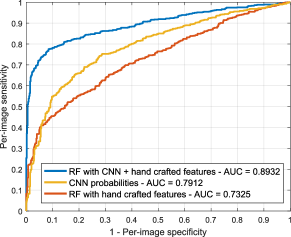

Figure 11(a) illustrates the ROC curves for DR screening on MESSIDOR, obtained using our hybrid representation and each of the approaches separately. CNN results were obtained using the network as a classifier. A series of Mann-Whitney tests () were performed to study the statistical significance of the differences in the AUC values (Hanley and McNeil, 1982). CNN features (AUC ) perform significantly better () than hand crafted features (AUC ) for this specific task, and the combination of both sources of information results in a substantially higher AUC value of 0.8932 (). Figure 11(b) shows analogous behavior for detecting patients that need referral, with the CNN performing better than the hand crafted features (), and the combined approach outperforms both individual techniques ().